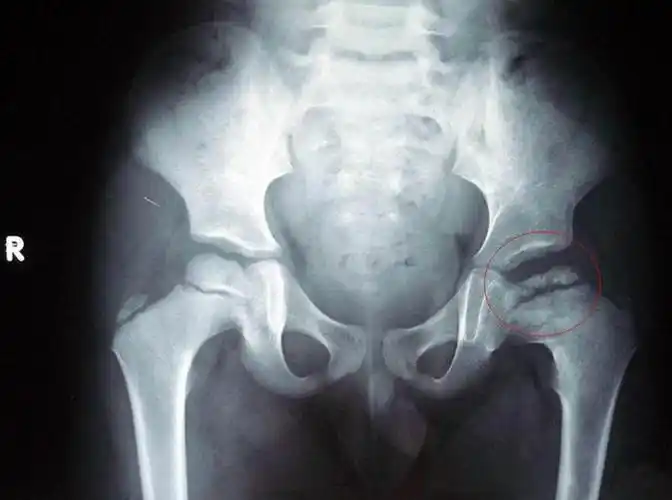

秀山医院超声科为小儿谋福利啦——小儿髋关节检查

婴儿出生不久,髋关节就脱位?若出现以下情况,家长需要警惕

小孩子发生髋关节发育不良的原因有哪些?襁褓真的会加重吗?

先天性髋关节脱位_疾病介绍_治疗方法 - 好大夫在线

警惕儿童髋关节疼痛股骨头坏死你知道多少

宝宝腿纹臀纹不对称就是髋关节发育不良吗为啥说越早发现越好